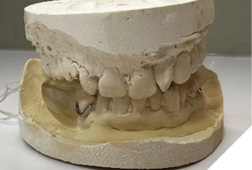

After informed consent, Phase I began with delivery of a Gelb appliance (Fig. 3ABC), which was adjusted periodically until achieving the treatment VDO. Phase II involved stabilization at this VDO. Teeth 36, 35, 43, and 44 were prepared simultaneously, and impressions (Henry Schein VP MIX) and bite registration (Kopy ultra-fast VPS) were taken using the palatal jig.

Fig. 3B

Fig. 3C

Temporary crowns (Maxitemp HP) compatible with the Gelb appliance were placed. Ten days later, single zirconia crowns (Argen YZ; Shaw Lab, Kingston, Ontario) were permanently cemented using 3M Ketac Cem. Teeth 34 and 33 were built up with composite (Activa, Pulpdent) to restore occlusal contact at the treatment VDO (Fig. 4).